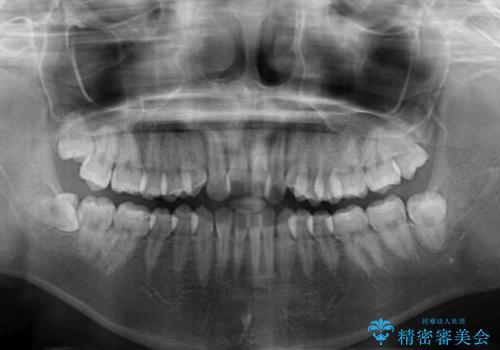

- 前歯のクロスバイトが気になり、インビザラインによる矯正治療を希望して来院された患者様です。

上顎側切歯(上の真ん中から2番目の歯)が舌側転位している場合、インビザラインでは仕上げきれないことが多く、更には無理して動かそうとすると歯髄壊死を起こすリスクが高いと言われています。

インビザラインで歯列を移動する前に、上顎前歯をワイヤー矯正で整え、その後上下歯列をインビザラインにて矯正治療を行うこととしました。

舌側転位している側切歯特有の、切縁の位置が不揃いであったり、根元が内側に引っ込んだ状態であったりという、インビザライン独特の仕上がりになることなく、きれいに整った歯列とすることができました。